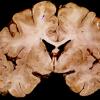

SSPE (2)